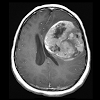

Radiology Flashcards: Neuro was designed for radiology resident and neuro imaging fellowship education. Physicians, residents, medical students, and anyone interested in pursuing a career in medical imaging will also find this app useful. Radiology Flashcards: Neuro provides the user with 100 high quality interactive images including plain film, CT, and MRI. On the opposite side of the flashcard is the correct diagnosis followed by a brief fact that can be memorized.Keep track of the items you missed, optimize your study time, and focus on high-yield clinically relevant concepts.In collaboration with Hawki, Inc, makers of Radiology Flashcards for iOS.